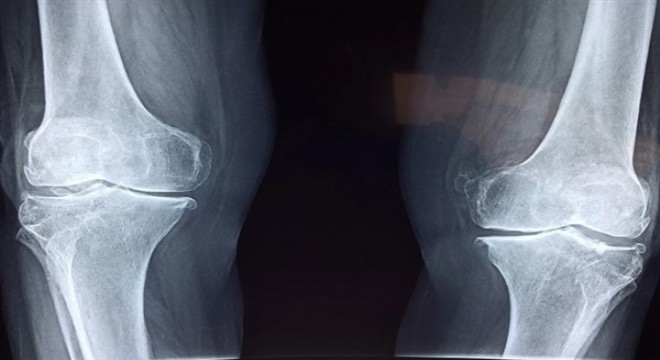

Glüten içeren besinlerle ilk karşılaşılan yer, enteron denilen ince bağırsakların içini döşeyen mukoza hücreleridir ki bunlara enterosit denir. Bu hücreler glütenin antijenik alt fraksiyonlarını tanıyıp, hemen arkalarında yerleşik olan bağışıklık sistemi hücrelerine bu antijeni sunarlar. Antikorlar, doku hasarına yol açan inflamatuar kimyasalların salgılanmasına neden olabilirler. Ayrıca antikorlar, moleküler taklit (moleküler mimikri) denilen bir işlemle, vücudun dokularıyla çapraz reaksiyona girerek otoimmün hastalıklar da denilen; Hashimato tiroidi, romatoid artrit, egzema, sedef, fibromiyalji gibi rahatsızlıklara neden olabilirler.